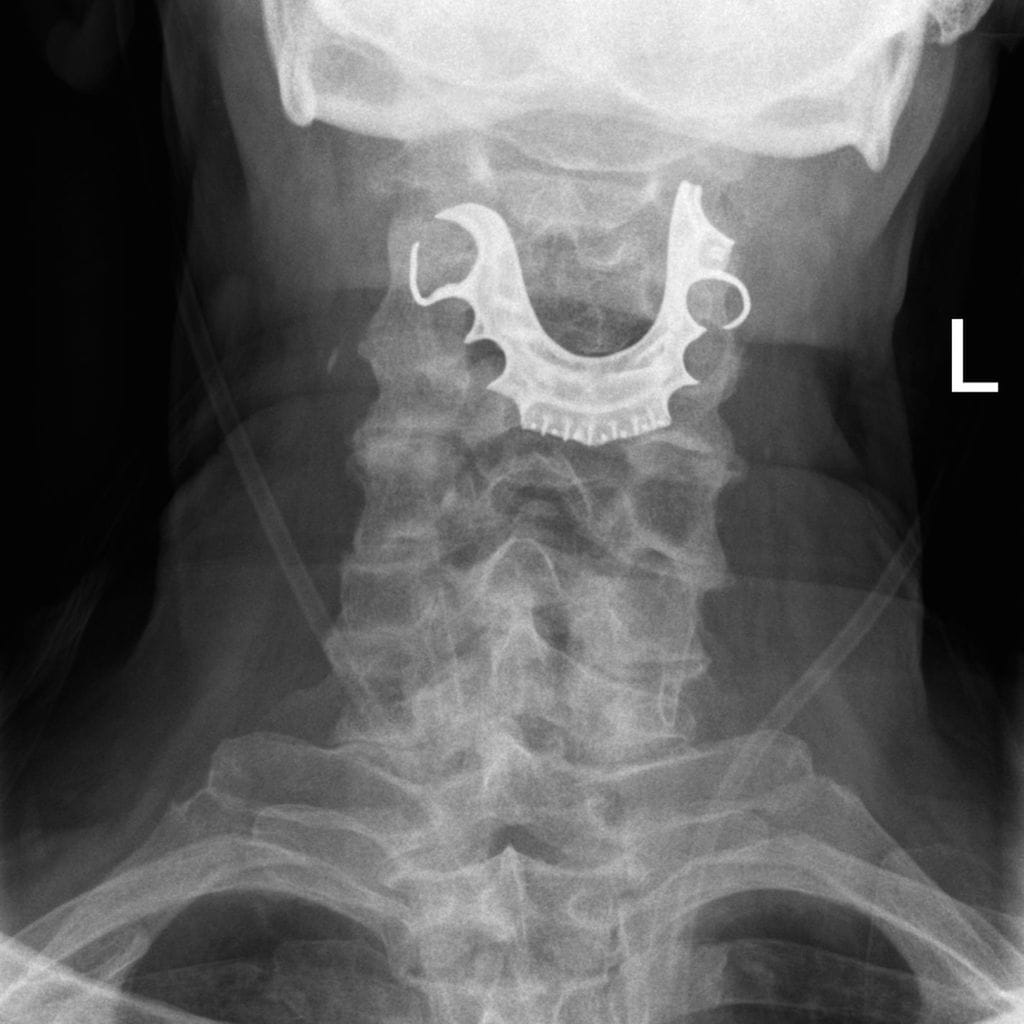

BMJ Case Reports -julkaisussa ilmestynyt tapausraportti kertoo 72-vuotiaasta miehestä, jonka hammasproteesi irtosi pienessä leikkauksessa. Miehen vatsanpeitteistä poistettiin hyvänlaatuinen kasvain. Lääkäritiimi ei ollut ottanut miehen tekohampaita pois ennen nukutusta.

Kuusi päivää myöhemmin mies joutui tulemaan päivystykseen. Hän kertoi suun verenvuodosta sekä hengitys- ja nielemisvaikeuksista. Mies ei ollut kyennyt syömään kiinteää ruokaa leikkauksen jälkeen.

Lääkärit eivät kyenneet diagnosoimaan syytä ongelmien takana verikokeista ja rinnan röntgenkuvauksesta huolimatta. Mies lähetettiin kotiinsa mukanaan resepti suuveteen, antibiootteihin ja steroideihin. Hänellä epäiltiin olevan alahengitystieinfektio ja kipuja leikkauksessa asetetun hengitysputken asentamisesta.